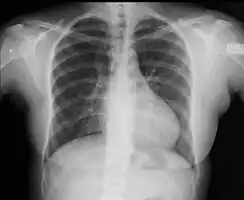

With imaging, resorption of the lower part of the ribs may be seen, due to increased blood flow over the neurovascular bundle that runs there. Prestenotic dilatation of the aortic arch and left subclavian artery, as well as indentation at the site of coarctation results in a classic 'figure 3 sign' on x-ray. The characteristic bulging of the sign is caused by dilatation of the aorta due to an indrawing of the aortic wall at the site of cervical rib obstruction, with consequent poststenotic dilatation. This physiology results in the '3' image for which the sign is named.[5][6][7] When the esophagus is filled with barium, a reverse 3 or E sign is often seen and represents a mirror image of the areas of prestenotic and poststenotic dilatation.[8]